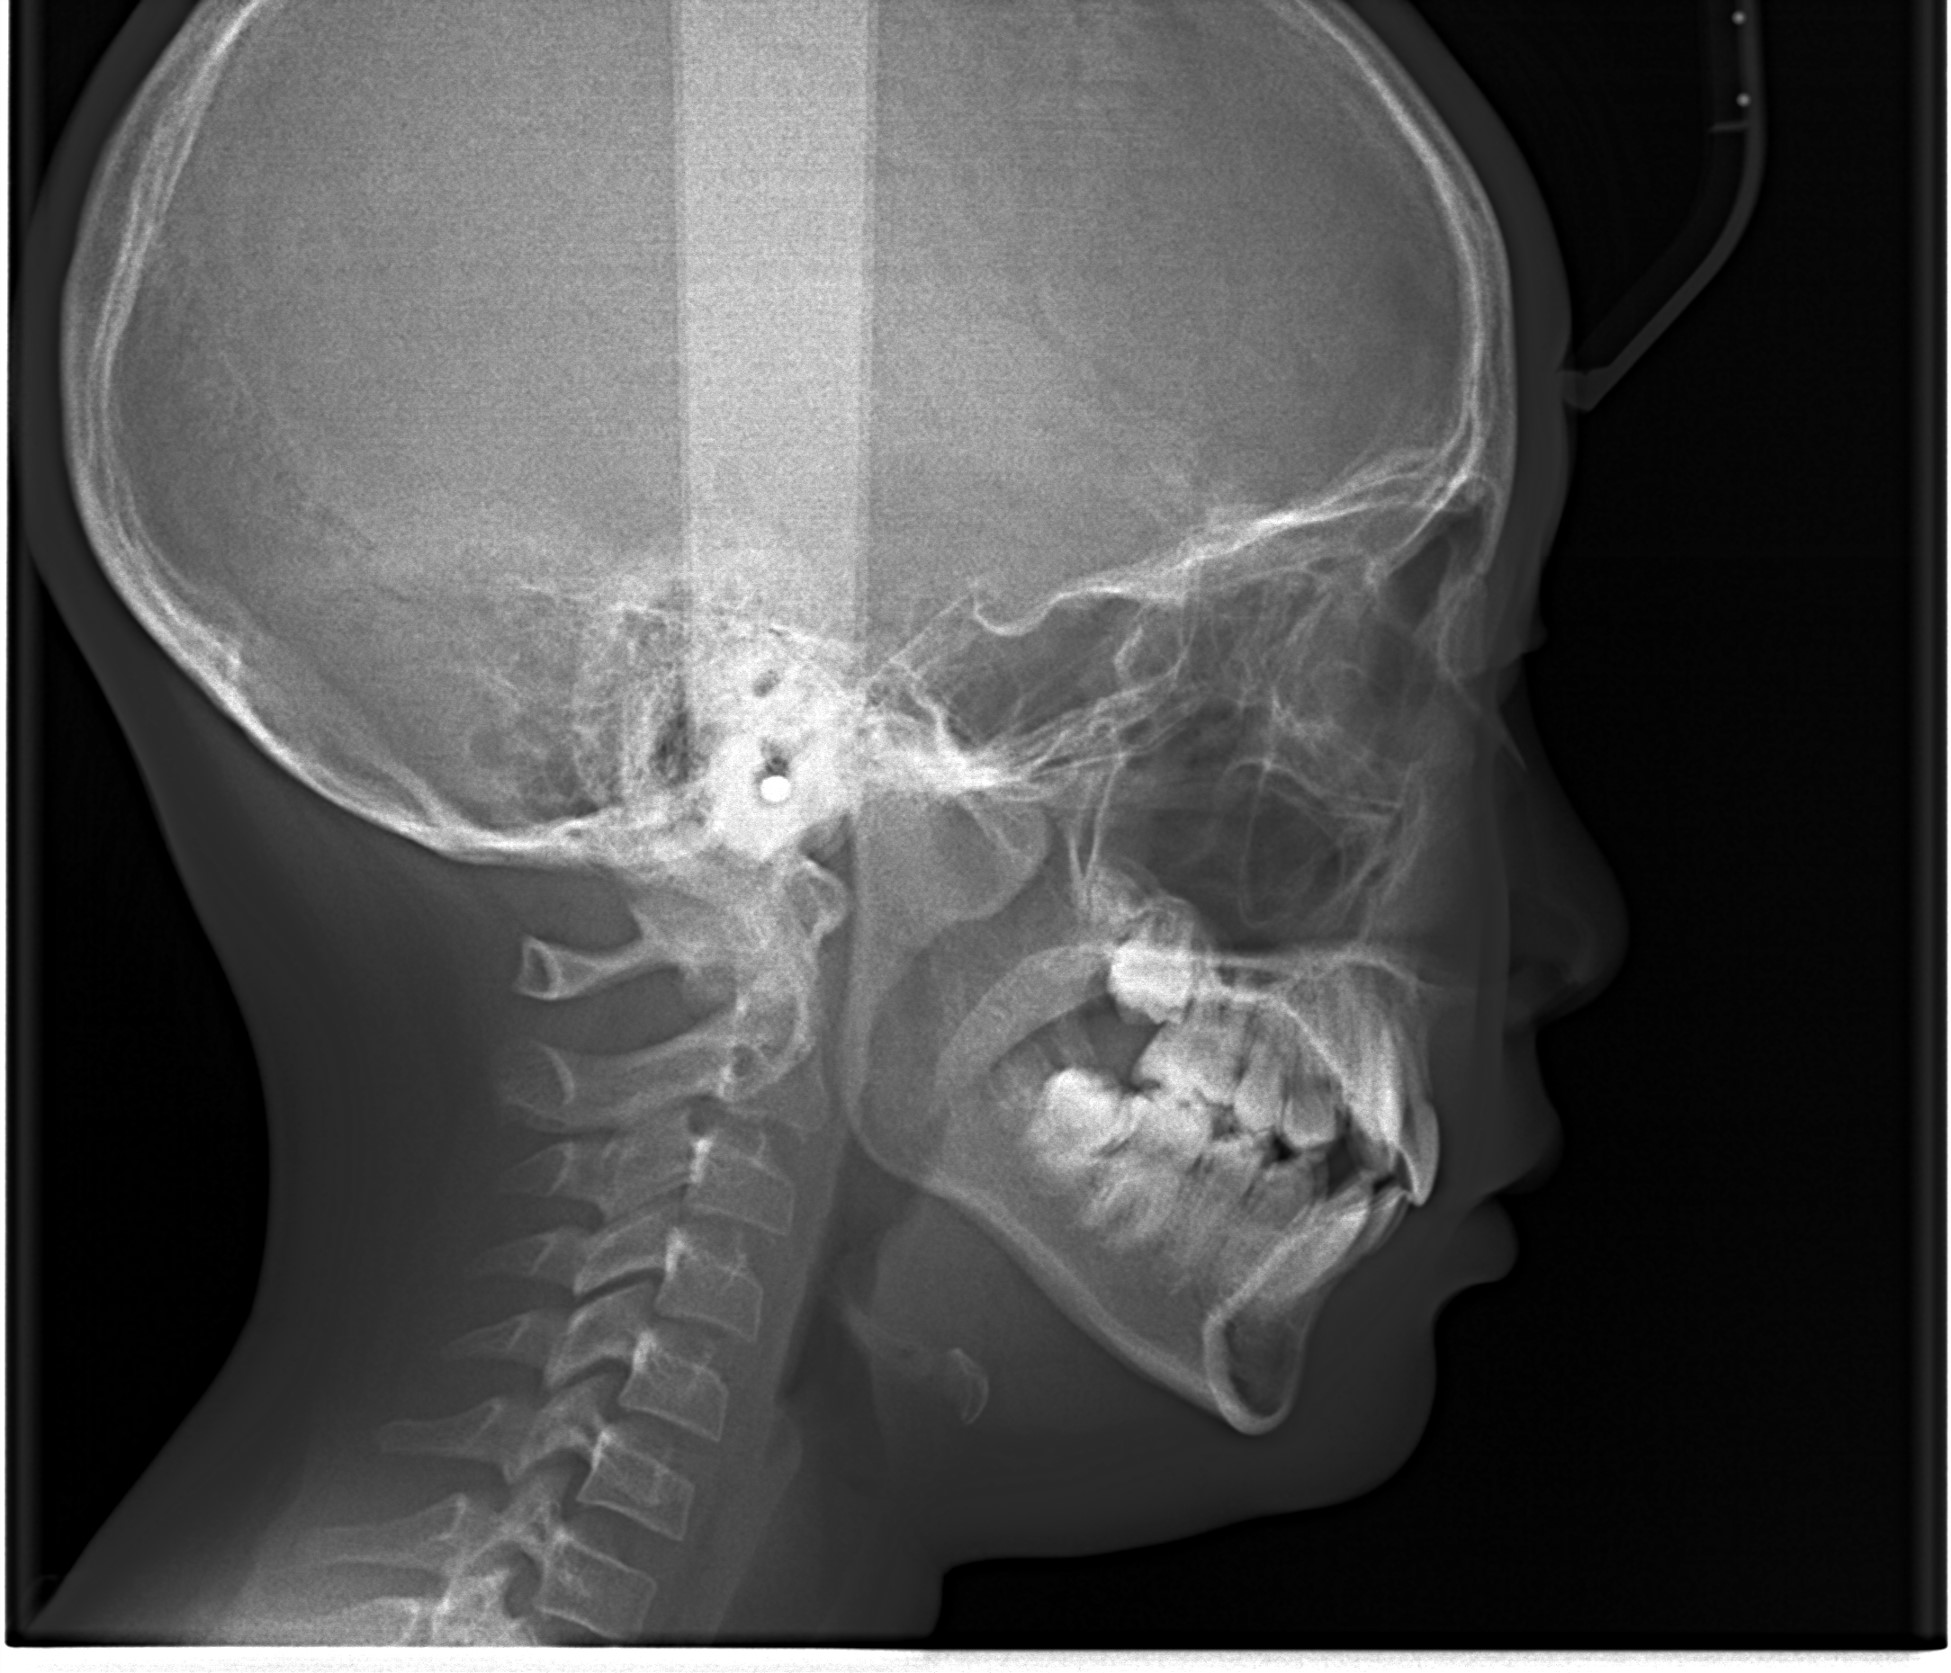

・エックス線検査

検査時のレントゲン写真、お口の中の写真、お顔の写真をもとに分析・診断を行い、歯列矯正治療の計画を立てていきます。